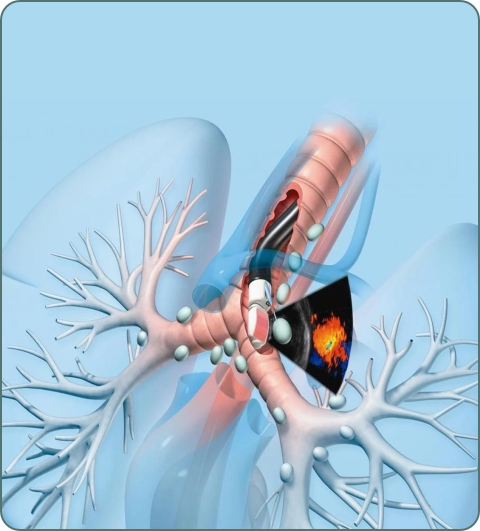

Bronchoscopy

Direct visualization of airways using thin camera. Used for diagnosis, biopsy, and treatment of lung conditions and infections.

Bronchoscopy Procedures

Minimally invasive procedures through bronchoscope including biopsy, stent placement, and foreign body removal.